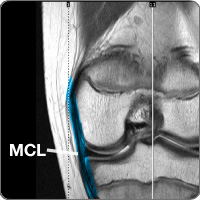

Medial collateral ligament injury

cond-media-collaThe knee contains the medial collateral ligament (MCL), one of four ligaments (tough band of tissue) connecting the femur (thigh) bone to the tibia (lower leg) bone. In combination with the lateral collateral ligament (LCL), the ligament on the outside of knee, the MCL lies on the medial (inside) of the knee joint and provides stability to the knee for side-to-side movement. The ligament becomes injured or torn when it is stretched beyond its normal range of movement.